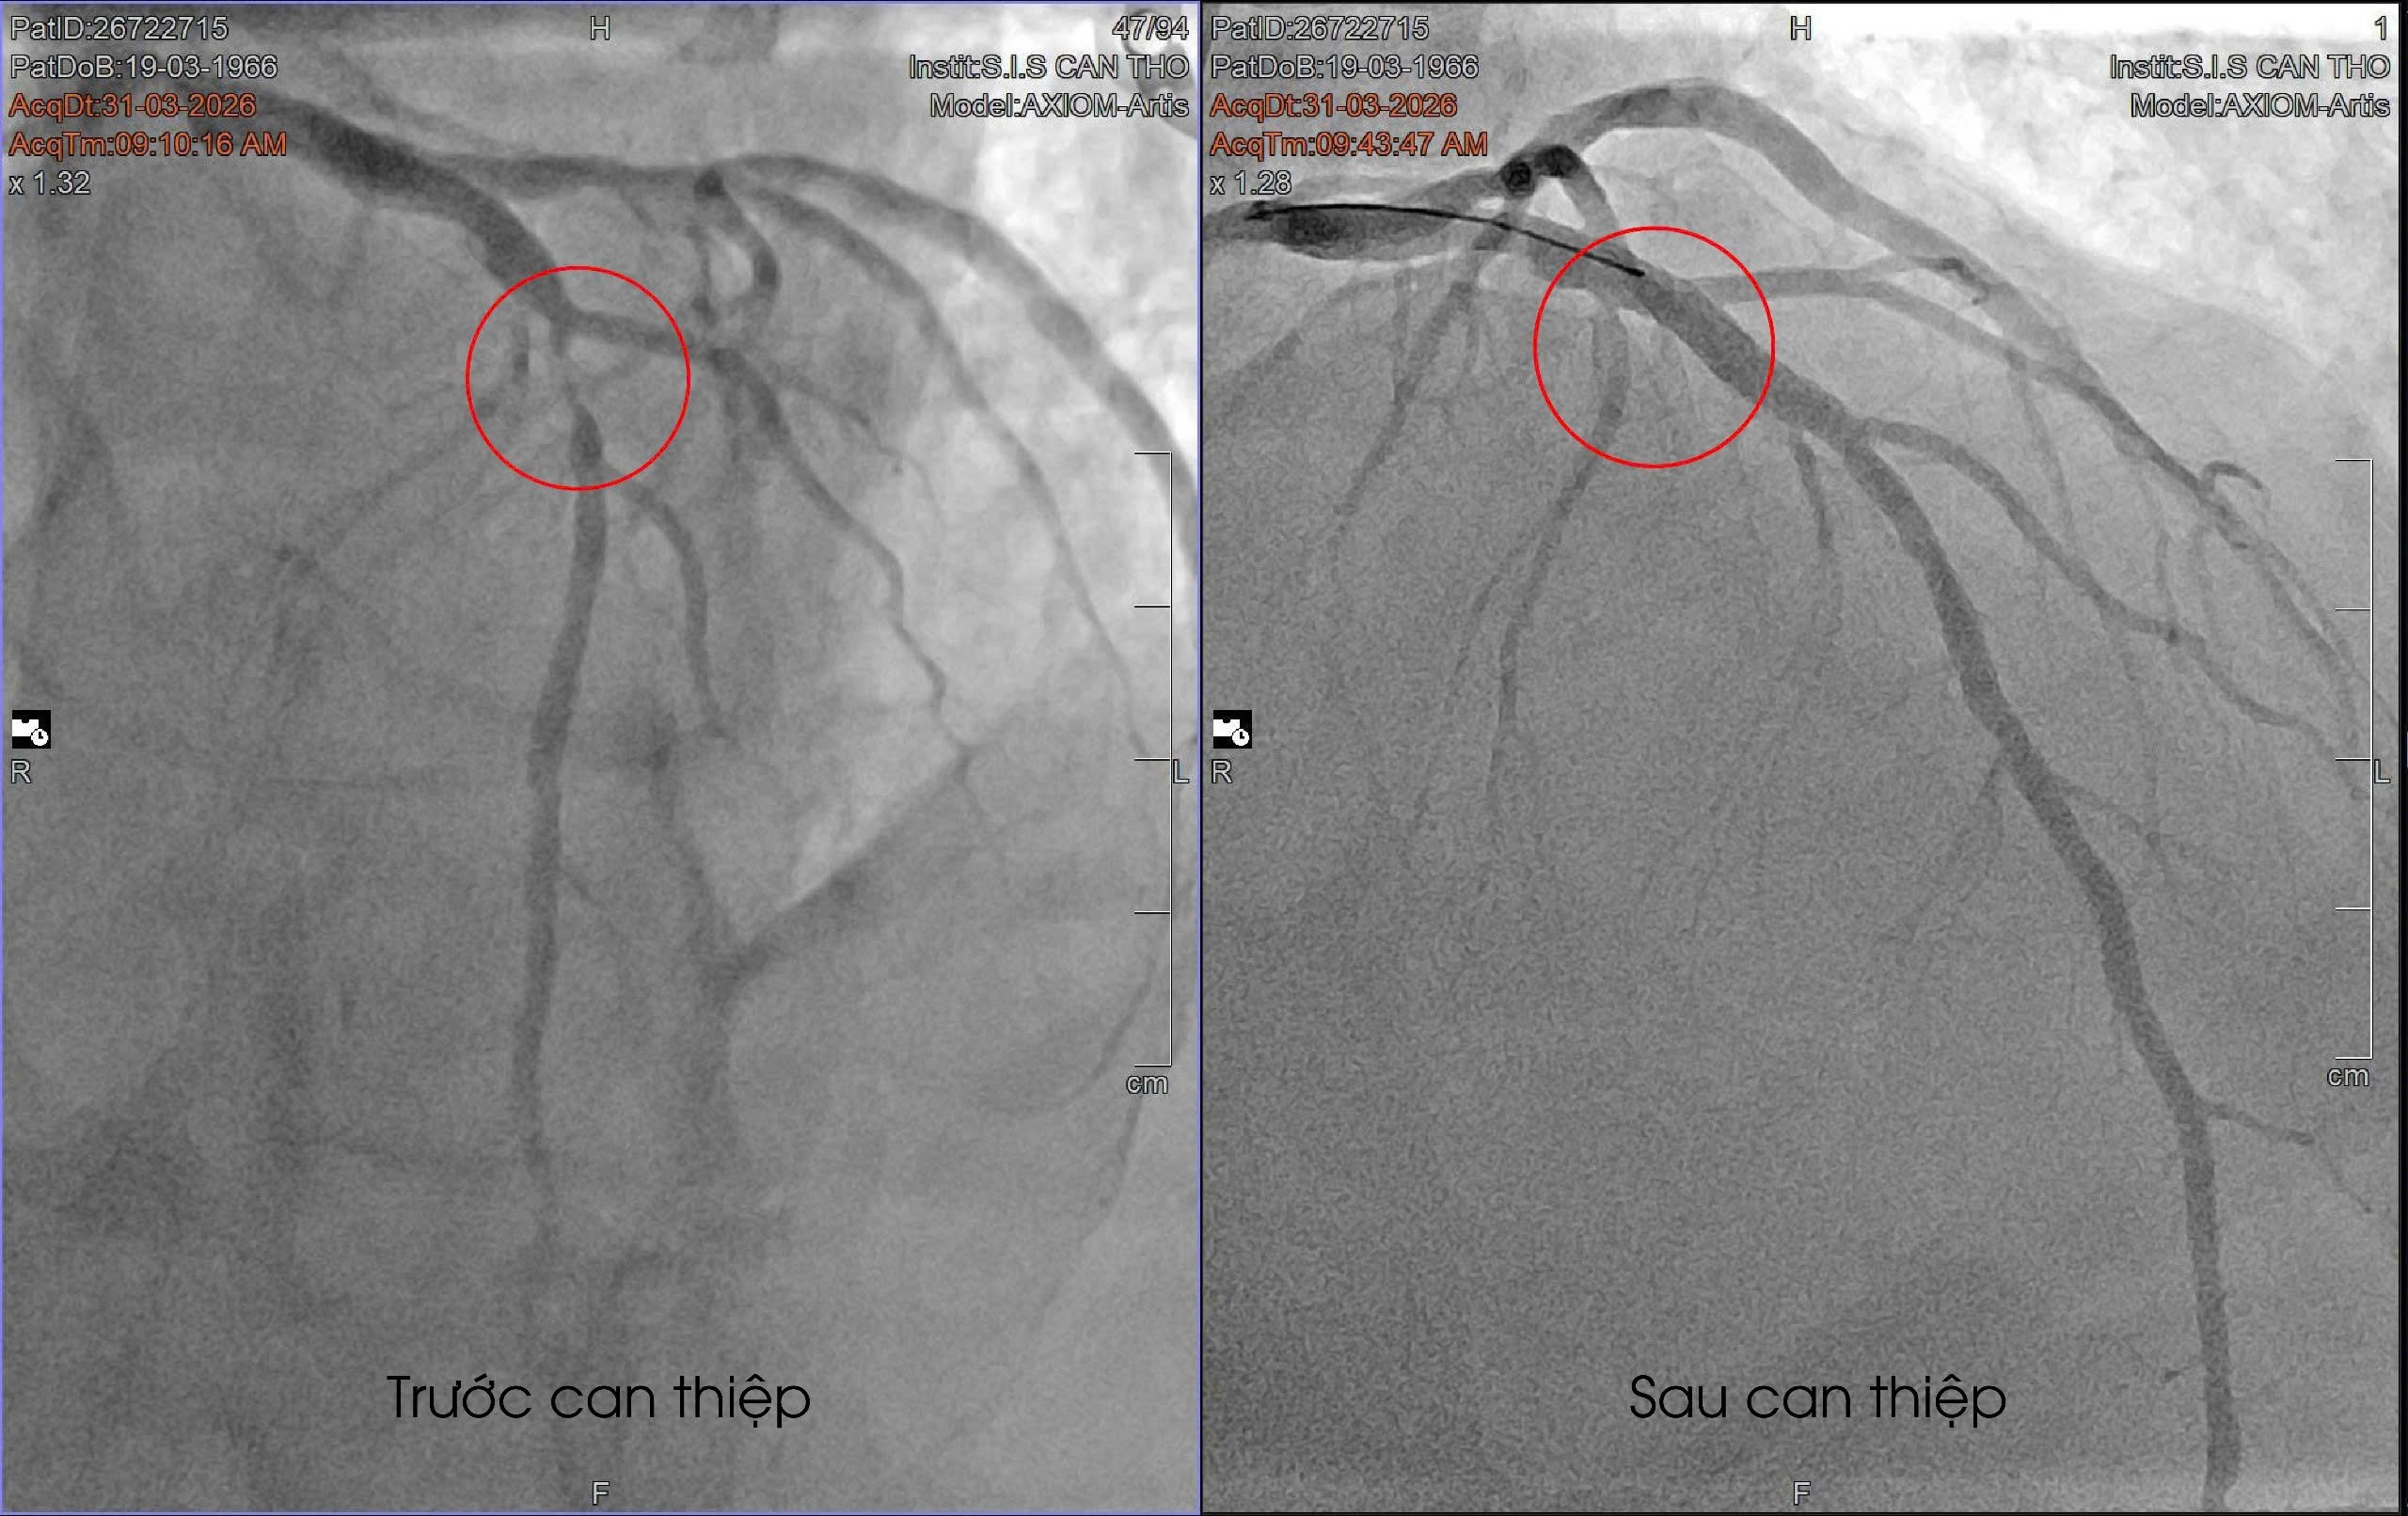

Bệnh nhân nhanh chóng được chỉ định chụp mạch vành bằng DSA. Kết quả khiến ê-kíp bác sĩ không khỏi lo ngại khi ghi nhận động mạch liên thất trước (mạch máu nuôi sống phần lớn cơ tim) bị hẹp nặng, gần như tắc hoàn toàn. “Đây là động mạch rất quan trọng, chi phối khoảng 50–60% cơ tim. Nếu tắc hoàn toàn, bệnh nhân có thể đột tử bất cứ lúc nào...” BS. Mai Hoàng Dil cho biết.

May mắn, trong trường hợp này, dòng máu vẫn còn lưu thông rất nhỏ “như sợi chỉ”, giúp bệnh nhân chưa rơi vào biến chứng nguy hiểm như đột tử. Ngay sau đó, bệnh nhân được chỉ định can thiệp đặt stent phủ thuốc, dưới sự hỗ trợ của siêu âm trong lòng mạch IVUS nhằm tối ưu hiệu quả điều trị. Sau can thiệp, các triệu chứng nhanh chóng cải thiện như hết đau ngực, không còn khó thở, sức khỏe hồi phục rõ rệt. Chỉ sau thời gian ngắn, bệnh nhân đã có thể đi lại, sinh hoạt bình thường.